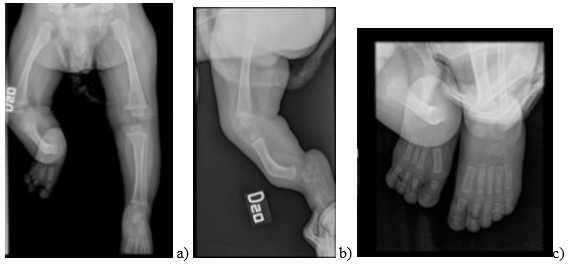

El primer caso documentado es de un bebé de 6 meses de edad, a quien en estudios prenatales se le había detectado ausencia del peroné derecho y oligodactilia por agenesia del quinto metacarpiano (figura 1). En el examen físico presentaba acortamiento del miembro inferior izquierdo con arqueamiento anterior de la pierna, pie equino valgo, oligodactilia e inestabilidad de la rodilla por hipoplasia del ligamento cruzado anterior (figura 2).

a y b) Ausencia completa del peroné derecho, así como arqueamiento anterior de la tibia y disminución en la longitud de la extremidad inferior derecha a expensas del componente tibial. c) Ausencia de los núcleos de osificación del hueso cuboides, primera cuña del pie derecho y quinto dedo